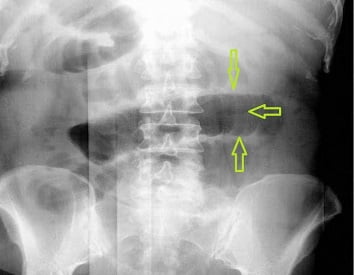

- рентгенологическое исследование кишечника обязательно при постановке данного диагноза. При введении рентгеноконтрастного вещества в просвет кишечника можно определить уровень развития кишечной непроходимости;